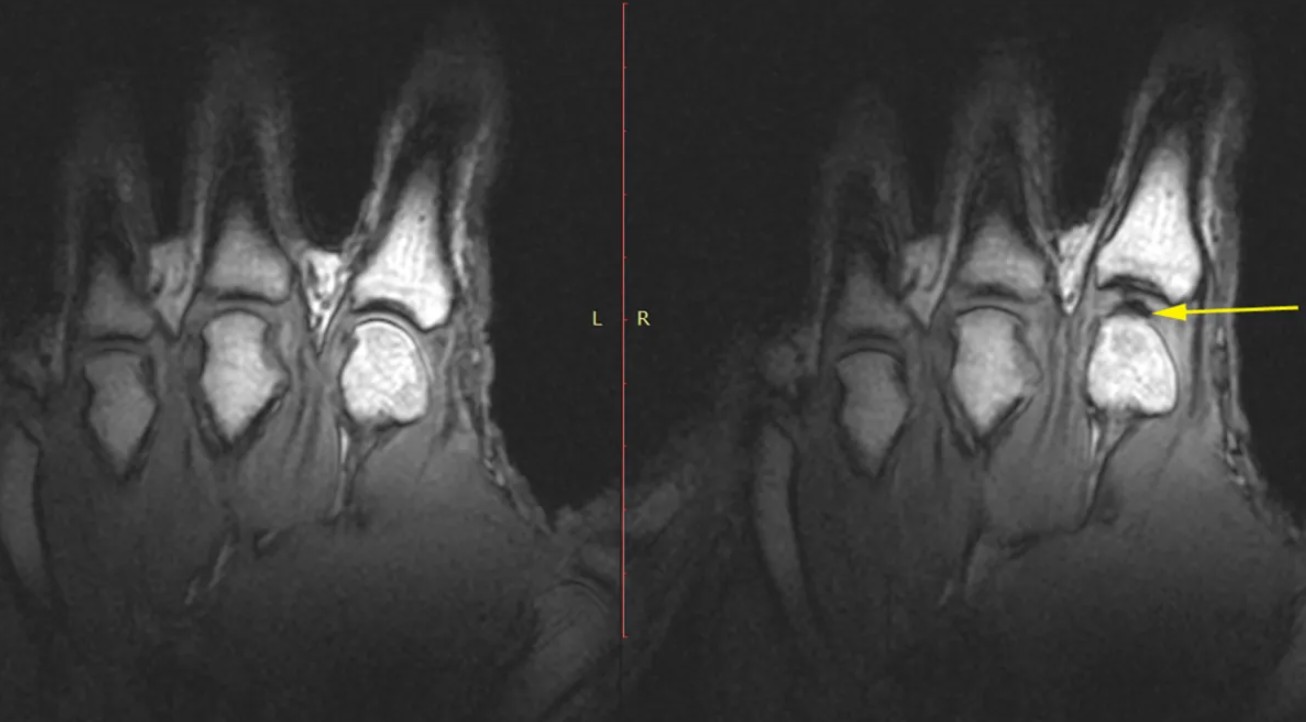

Ученые выяснили причину похрустывания пальцев. Для исследования они использовали геометрические изображения суставов и математические уравнения. Как пишет Independent, над исследованием работал ученый из Индийского института науки Винет Чандран Суджа и профессор из лаборатории гидродинамики Политехнической школы в Палезо, что во Франции Абдул Баракат. 24tv.ua »